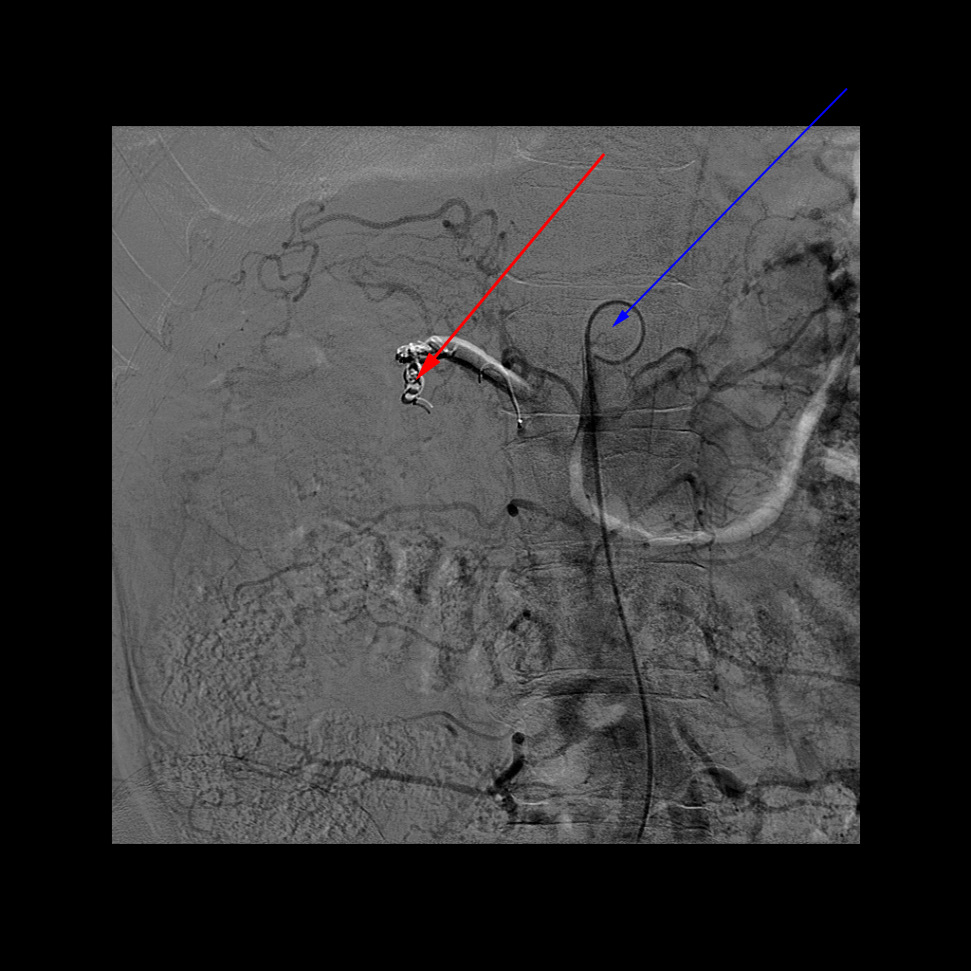

Billedet viser en aflukning af blodforsyningen til nyretumor (embolisation). Der lægges coils (rød pil) i pulsåren til tumoren, hvorefter den ikke ses. Kontrasten er sprøjtet ind via et kateter (blå pil).